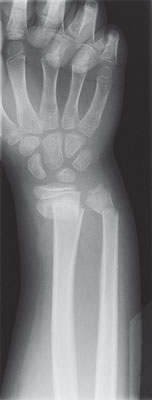

X-ray of a broken wrist |